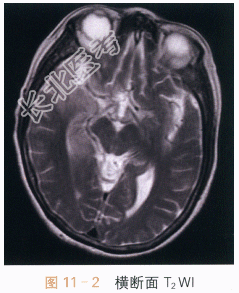

- [材料题] 患者,女,65岁,发热1周,伴神志异常2天。实验室检查:潘氏实验阳性,脑脊液白细胞计数升高,脑脊液蛋白升高。抗巨细胞病毒IgG阳性,抗单细胞病毒1型IgG阳性,抗EB病毒衣壳抗原IgG阳性。影像学资料及分析影像学资料如图11-1~图11-4所示。